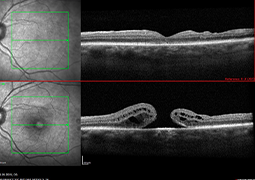

- Postradiačná makulopatia u pacientov s malígnym melanómom corpus ciliare a chorioidey po stereotaktickej rádiochirurgii